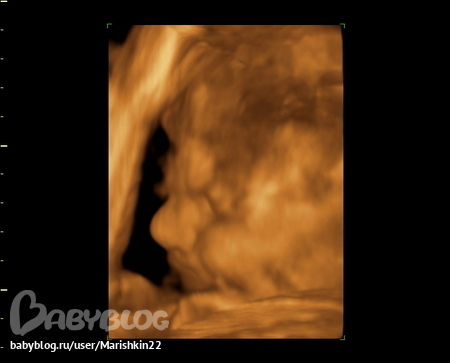

Ходили на УЗИ 3Д

Во время процедуры он дремал с недовольным таким выражением : нахмурился, щечки большие, кулак возле личика, потом каак зевнет. ))))) Большой уже такой, сладкий наш.

Под катом более-менее четкое изображение ))))